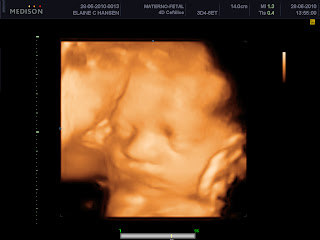

Esse é o Alan, visto com 29 semanas! Carinha de brabo (mas é porque foi muito cutucado pra tirar a mão do rostinho!). Lindo, maravilhoso como a irmãzinha dele! Isso aí filho, venha pra arrasar os corações das gatinhas!!!!

Alan em 4D